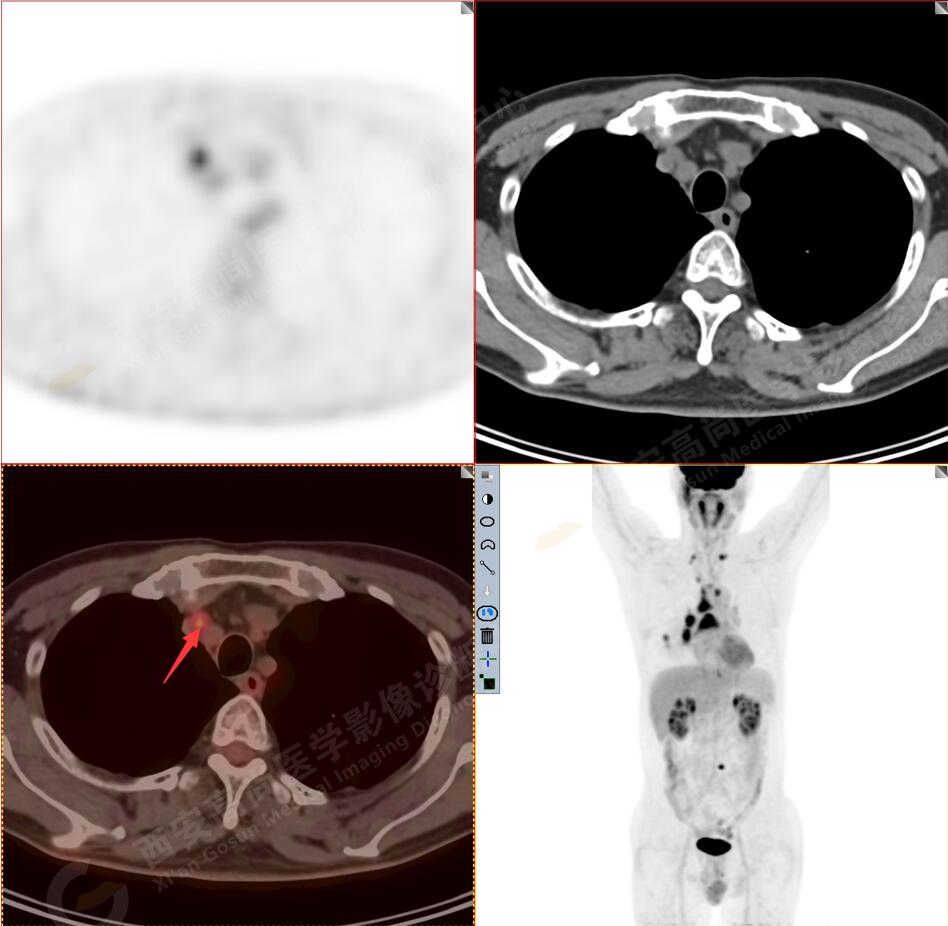

1.以下為肺內(nèi)原發(fā)灶

1.右肺下葉后基底段軟組織結(jié)節(jié)(約1.5cm×1.2cm),與相鄰后胸膜分界不清,呈FDG代謝異常增高,結(jié)合病理,符合肺腺癌伴鄰近胸膜侵犯。

3.右側(cè)肺門、縱隔(1L、1R、3A、4、6、7組)及雙側(cè)鎖骨上多發(fā)腫大淋巴結(jié),呈不同程度FDG代謝異常增高,考慮為淋巴結(jié)轉(zhuǎn)移。